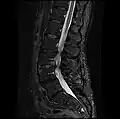

MRI lumbar spine with degeneration, post-hemilaminectomy L4-5 (sagittal T2 FRFSE) -

MRI lumbar spine with degeneration, post-hemilaminectomy L4-5 (sagittal T1 FSE) -

MRI lumbar spine with degeneration, post-hemilaminectomy L4-5 (sagittal FAST STIR) -